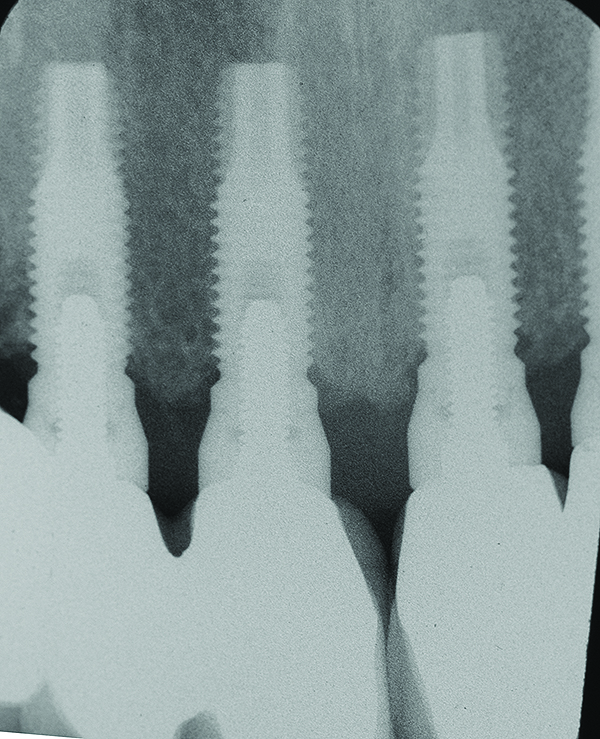

Fig 1 through Fig 6. Periapical radiographs of a 52-year-old man who received a fixed porcelain-fused-to-metal reconstruction supported by abutments attached to externally hexed dental implants. Fig 1 through Fig 3 are at initial prosthesis placement: maxillary right (Fig 1), textured surfaced threaded titanium implants at site Nos. 2, 4, and 6; maxillary anterior (Fig 2), implants at site Nos. 7 through 9; maxillary left (Fig 3), implants at site Nos. 12 and 14. Fig 4 through Fig 6 are 10 years post-insertion of the prosthesis: maxillary right (Fig 4), maxillary anterior (Fig 5), and maxillary left (Fig 6). Note minimal to no bone loss radiographically around the implants 10 years post-insertion of prosthesis.